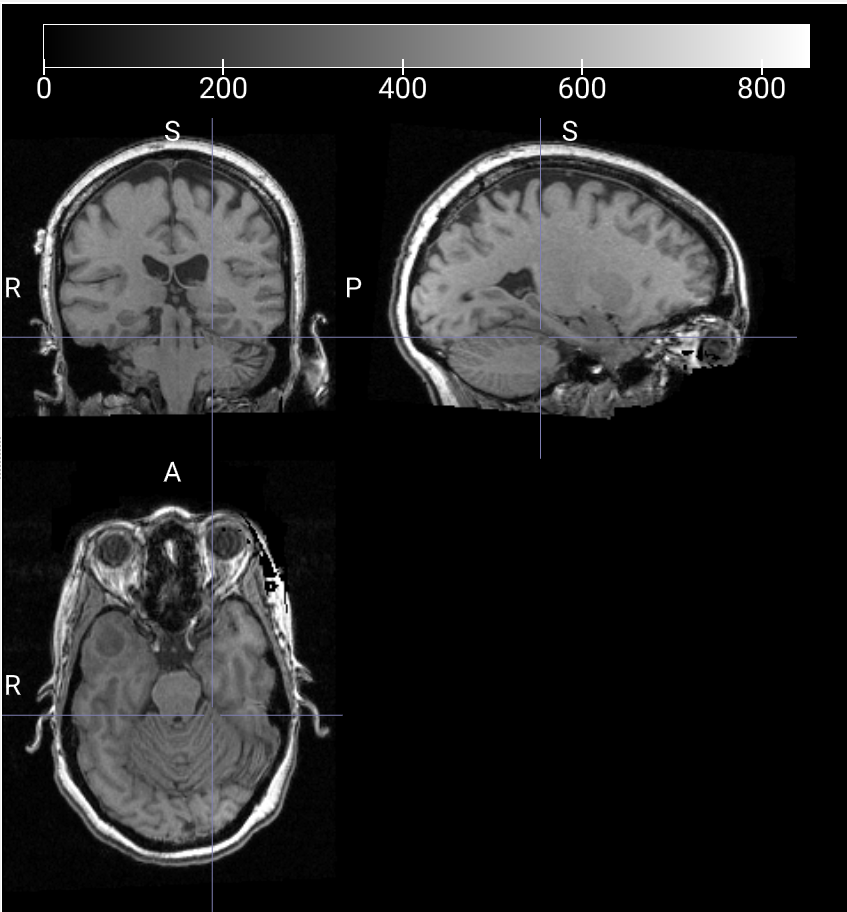

数据样本可视化

T1W 3D 对比度增强图像